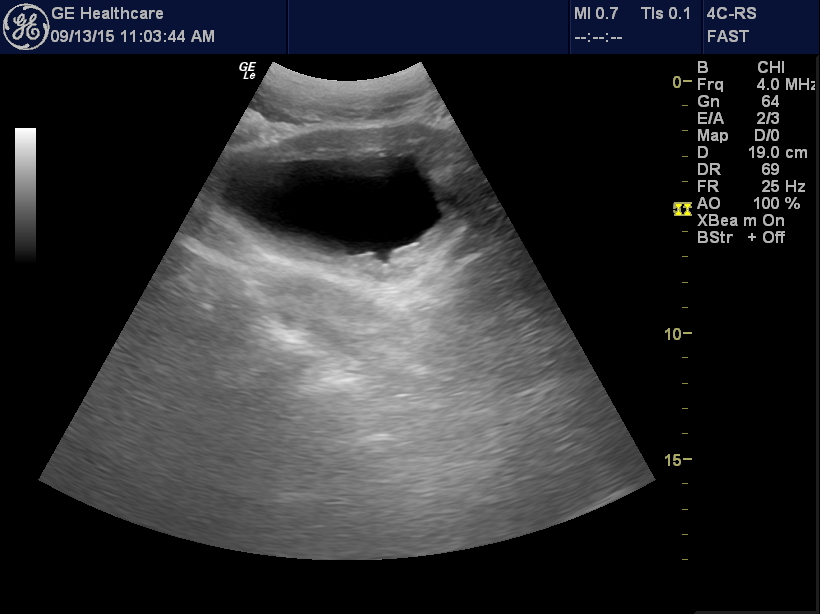

This patient came in for constipation. He was older so I checked for

retention. Sure enough his bladder was big-800+cc.